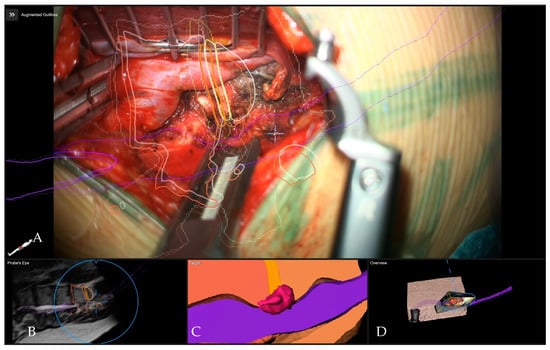

Surgical Treatment of Calcified Thoracic Herniated Disc Disease via the Transthoracic Approach with the Use of Intraoperative Computed Tomography (iCT) and Microscope-Based Augmented Reality (AR)

5.1. Surgical Technique and Outcome for Resection of Calcified Thoracic Disc

5.4. Applications of Augmented Reality for Degenerative Spine Surgery